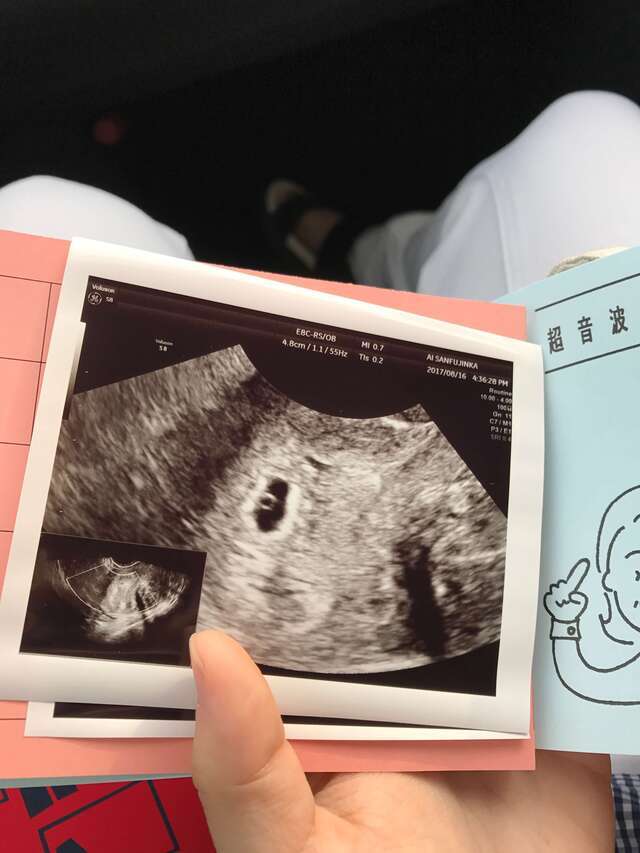

4週3日(4w3d・男の子)|みら20181101さん(36歳)

エコー写真撮影時のエピソード:

不妊治療をしてようやく授かって産院に移ってからのはじめてのエコー写真です!不妊治療の病院では毎週エコーをとっていたけれど産院に移ってから1ヶ月に1回になって毎回毎回不安で不安で祈るような気持ちでパパと一緒に通いました。つわりもひどかったけれど元気で産まれてきてくれて本当にうれしいです!